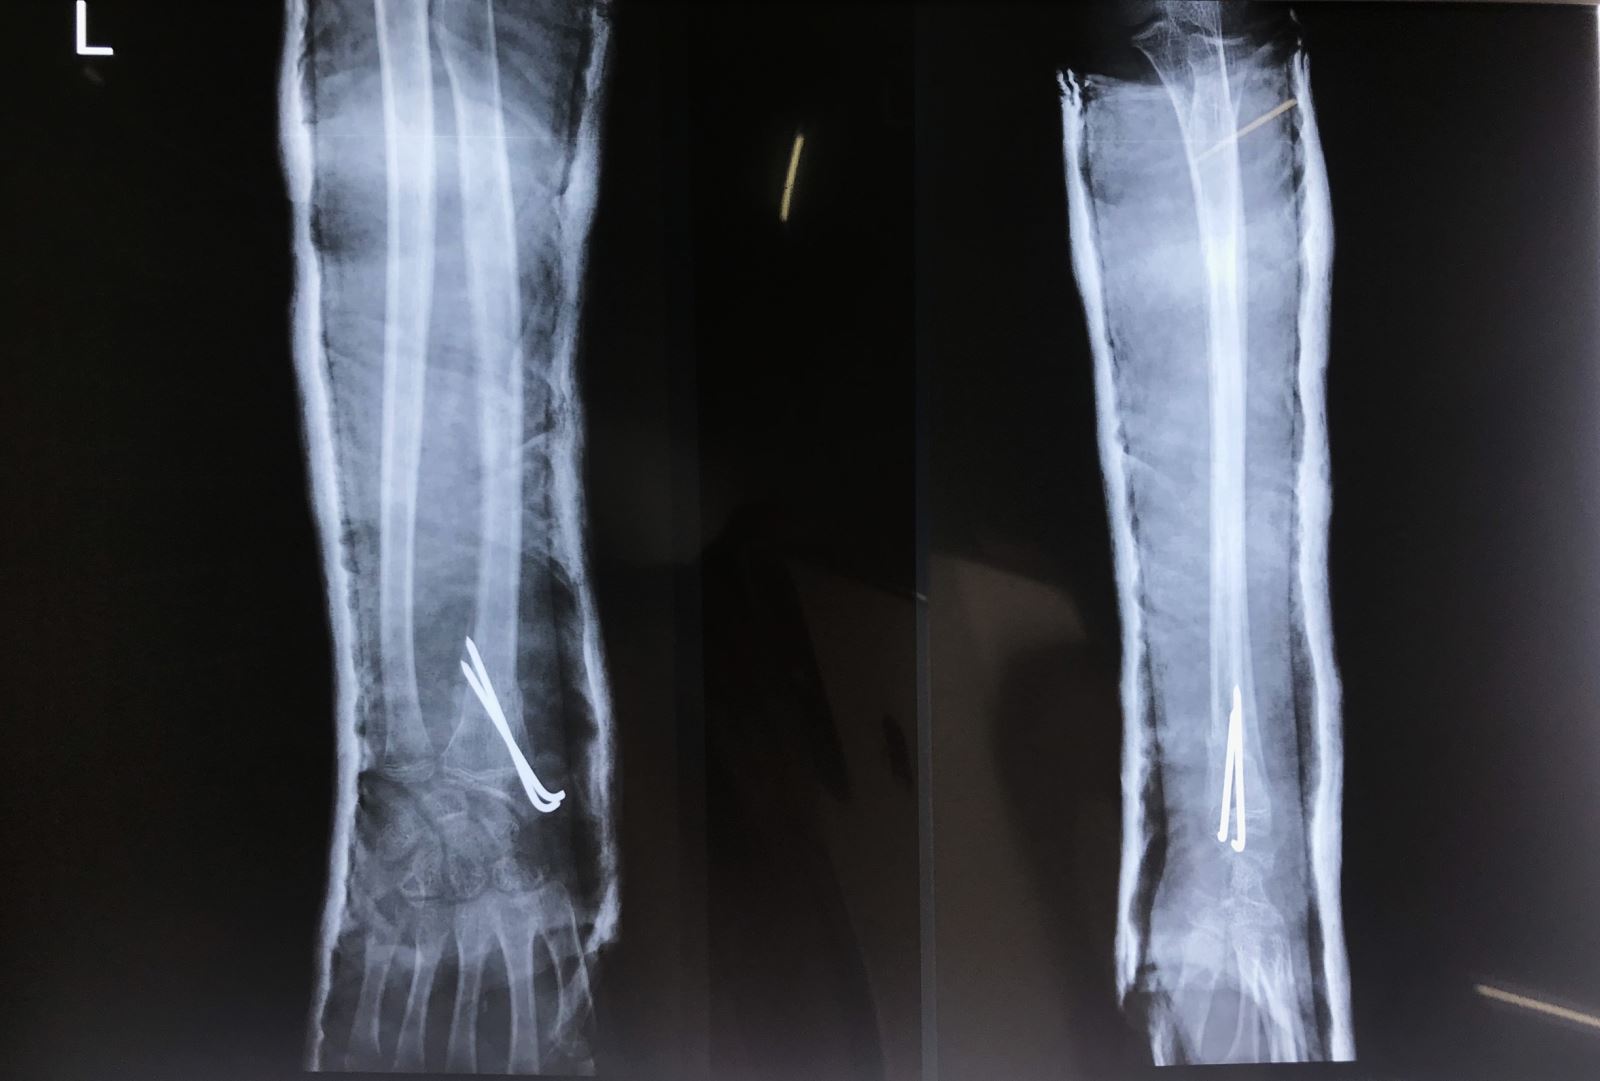

1. Nắn kín và xuyên đinh qua da dưới màn hình tăng sáng

2. Mổ hở nắn chỉnh và cố định bên trong: Nắn kín thất bại